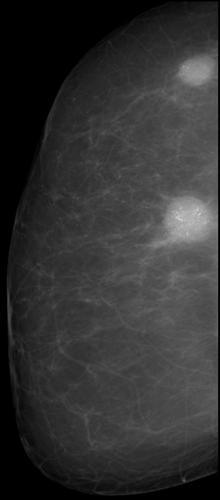

Лучевая диагностика патологии молочной железы (маммография)